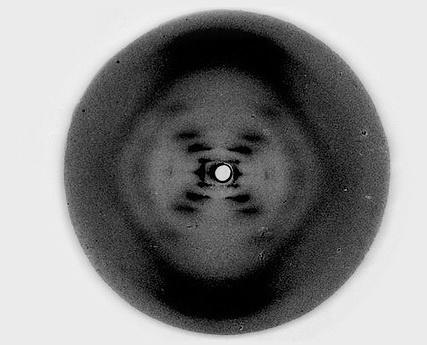

Рентгеновский снимок ДНК

Открытие двуспиральной структуры ДНК произошло после того, как Уотсон и Крик увидели рентгеновский снимок молекулы ДНК, сделанный Розалинд Франклин. На этом снимке они увидели признаки спирали, после чего пошли в лабораторию, чтобы проверить это на объёмной модели. Предложенная Уотсоном и Криком модель ДНК оказалась верной, и в 1962 году им вручили Нобелевскую премию. Среди лауреатов не было лишь скончавшейся к тому времени Розалинд Франклин, автора снимка.